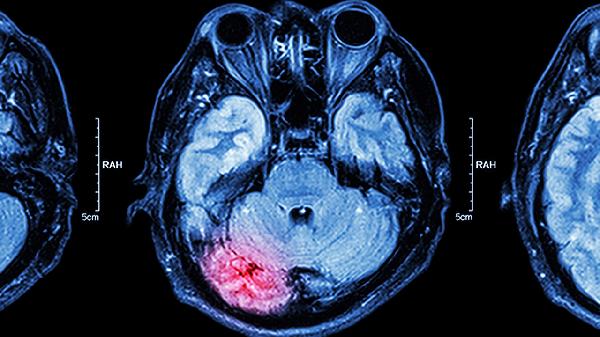

脑发育不良患者需建立长期管理计划,定期评估发育里程碑。家长应学习护理技巧,创造安全居家环境,避免跌倒等意外。保持规律作息,结合水疗、音乐疗法等多元刺激。社区康复与机构训练相结合,关注心理健康,必要时进行心理疏导。建议每3-6个月复查脑电图、头颅MRI等检查,动态调整治疗方案。